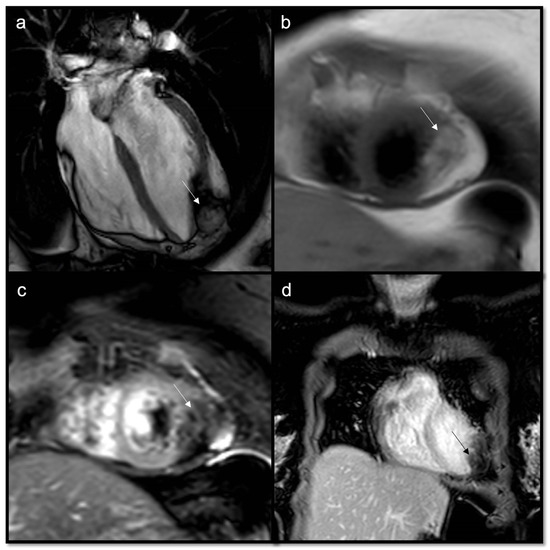

- To recognize fluid content such as a pericardial cyst or myocardial cyst (Figure 3)